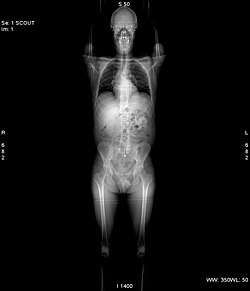

Aufnahmemodi

Vor jeder Aufnahme wird grundsätzlich eine Übersichtsaufnahme aufgenommen. Hierbei steht die Röntgenröhre still. Der Patient wird mit Hilfe des verfahrbaren Tisches am Fächerstrahl der Röhre vorbeigefahren. Im Ergebnis erhält man ein Bild, das einer klassischen Röntgenaufnahme sehr ähnlich sieht. Dieses Bild dient jedoch nur der Planung anschließender Aufnahmen.[1]